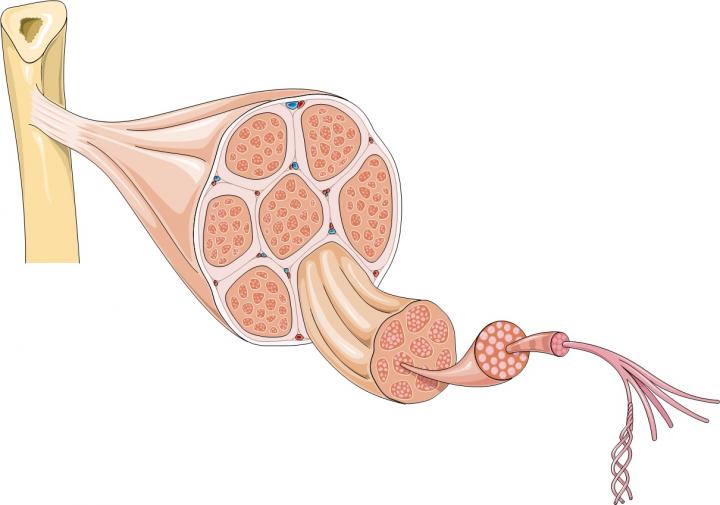

肌肉的大部分由肌纖維束形成,長(zhǎng)細(xì)胞含有許多細(xì)胞核;但肌肉也含有許多其他類型的細(xì)胞,包括干細(xì)胞。干細(xì)胞是人體內(nèi)置修復(fù)系統(tǒng)的一部分。它們可以產(chǎn)生祖細(xì)胞,也可以復(fù)制自己。骨骼肌含有一種稱為衛(wèi)星細(xì)胞的干細(xì)胞。當(dāng)肌肉纖維受損時(shí),它們會(huì)向衛(wèi)星細(xì)胞發(fā)送化學(xué)信號(hào),告訴它們形成新的肌肉纖維或與現(xiàn)有纖維融合以修復(fù)損傷。同時(shí),一些衛(wèi)星細(xì)胞會(huì)自我復(fù)制,以確保有足夠的干細(xì)胞可用于在未來(lái)繼續(xù)修復(fù)和更換肌肉纖維。

Emma Kemp 使用Servier Medical Art制作的肌肉結(jié)構(gòu)主圖和說(shuō)明 iPS 細(xì)胞在肌營(yíng)養(yǎng)不良癥細(xì)胞療法研究中的應(yīng)用?。Edwin P. Ewing, Jr 博士拍攝的杜氏肌營(yíng)養(yǎng)不良癥患者的肌肉圖像,由美國(guó)衛(wèi)生與公眾服務(wù)部公共衛(wèi)生圖像庫(kù)提供?。Mike Kayser的肌纖維照片?,Wellcome Images。?

從中成血管細(xì)胞中生長(zhǎng)的肌纖維由 OptiStem 和 Giulio Cossu 提供。